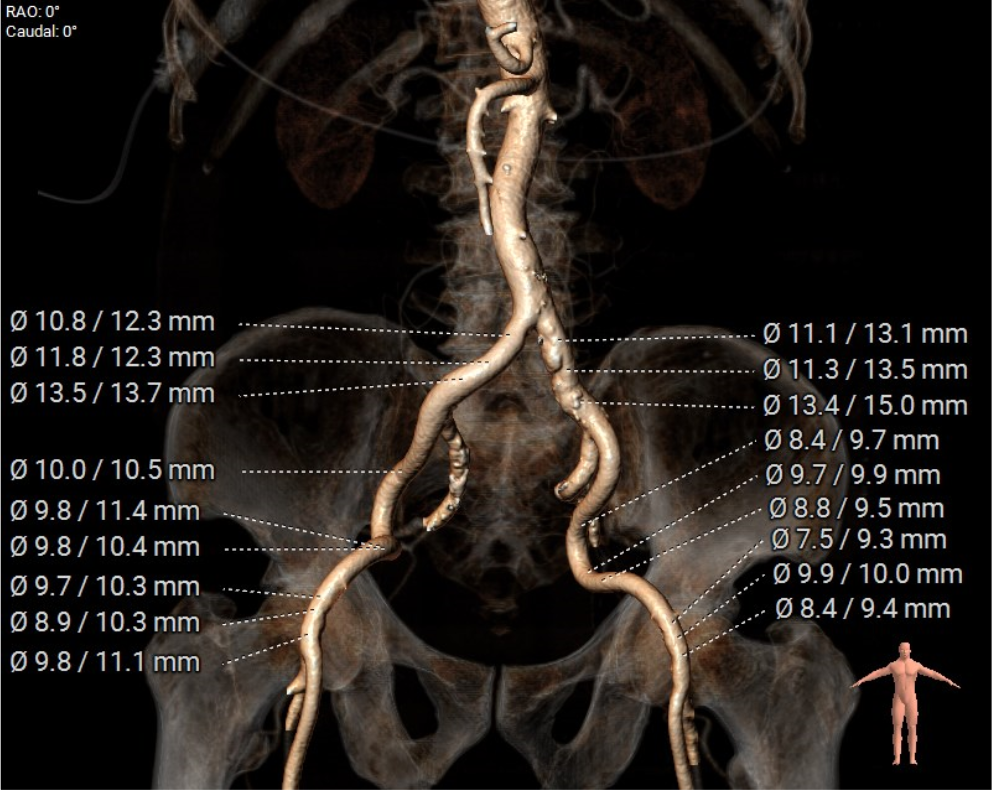

股动脉入路: